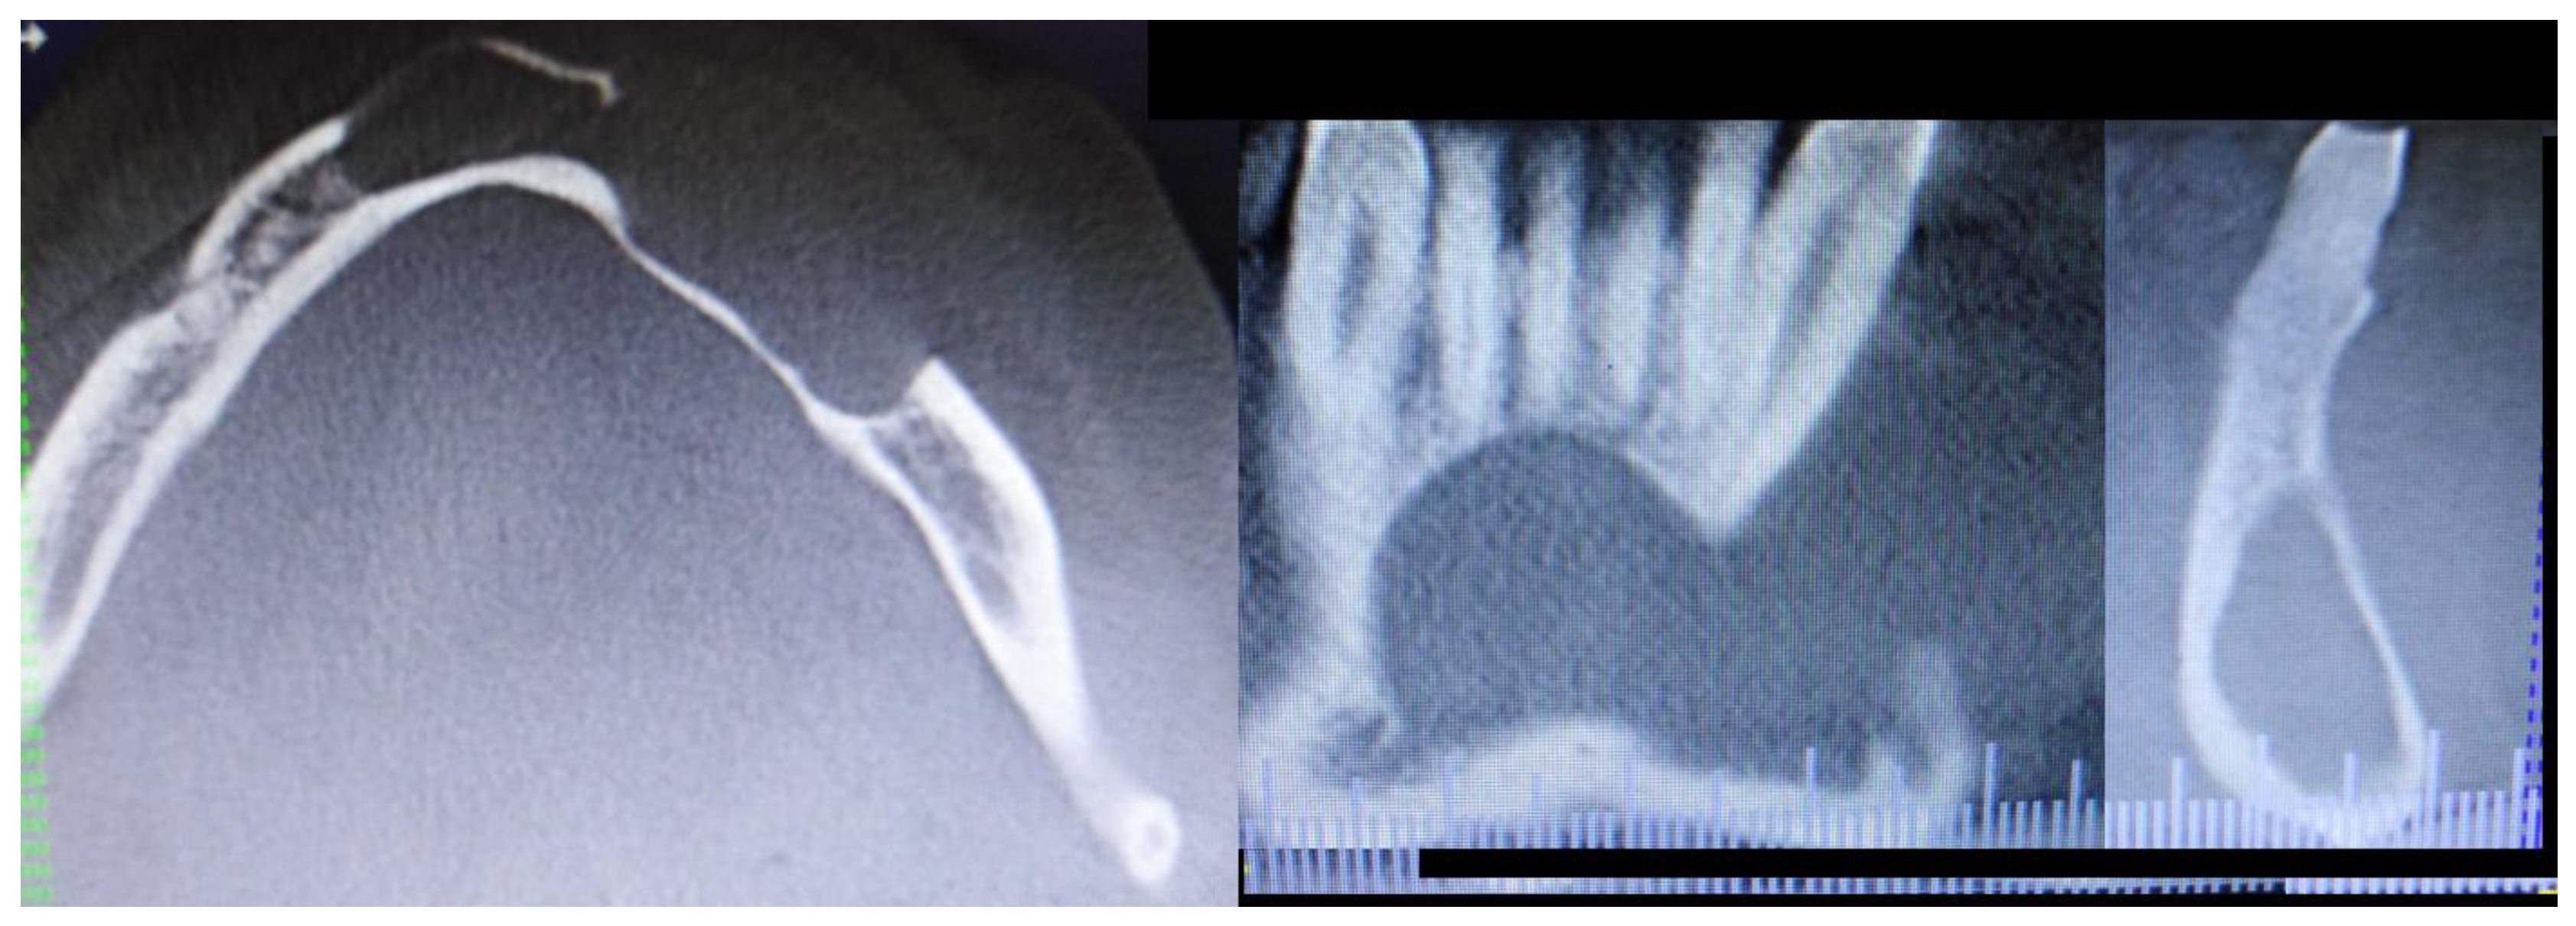

A 62-year-old Caucasian male was referred for consultation because of a cyst in the mandibular anterior and left body area associated with teeth mobility. The lesion was incidentally discovered by a dentist on a routine panoramic radiograph. On imaging, there was a polycystic lesion, quite big in diameter, with well-defined borders, visible inner cystic septa, and displaced 33,34,35 teeth. The cystic cavity ranged from tooth 43 towards 36, causing superior destruction of the alveolar ridge between teeth 33 and 34 and inferiorly spreading closely towards the inferior margin of the mandible. This expansive lesion was radiolucent with some septa with cortical buccal and alveolar ridge expansions (Figure 1).

Figure 1. A panoramic radiograph reconstruction based on CBCT imaging with visualized cystic cavity.